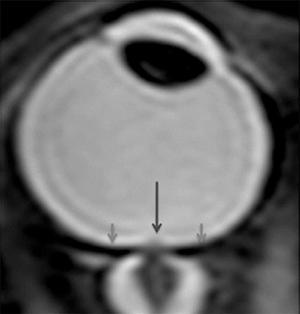

El motivo del aumento de hipermetropía no está del todo claro. Se ha propuesto que se debe a un acortamiento del globo ocular porque en situaciones de microgravedad, los fluidos corporales se concentran en la cabeza, aumentando la presión intracraneal y ejerciendo una fuerza sobre la parte posterior de los ojos, como se puede ver en la siguiente imagen.

Acortamiento del globo ocular por presión en la parte posterior, lo que genera hipermetropía